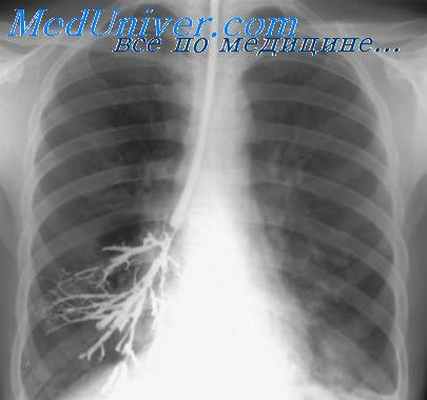

При бронхографии обнаруживается, что бронхи нижней зоны или доли расширены и сближены между собой. Бронхи язычка и остальных сегментов верхней доли смещены и раздвинуты. При вовлечении в воспалительный процесс язычковых бронхов они также цилиндрически расширены и сближены между собой и с бронхами нижней доли. Бронхи верхней зоны веерообразно раздвинуты.

Мешотчатые бронхоэктазы на бронхограммах видны в виде слепо заканчивающихся, резко расширенных бронхов IV—VI порядков, сближенных между собой и лишенных боковых ветвей (рис. 1).